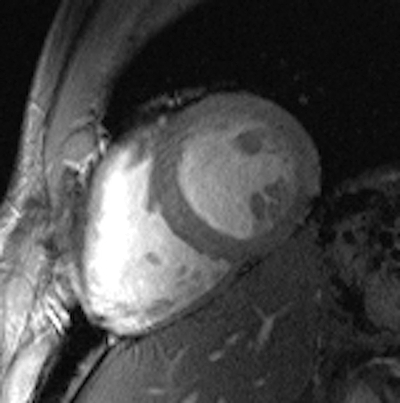

All these efforts culminated in images of the beating heart with a spatial resolution that is by a factor of five superior to that routinely available at 1.5 tesla, and which might come close to turning a 10-megapixel digital camera into a 50-megapixel digital camera. These improvements offer detailed insights into cardiac anatomy and allow accurate delineation of myocardial borders, a feature that is essential for cardiac chamber quantification.

Cine images (left: four-chamber view, middle: short-axis view, right: two-chamber view) of the beating heart acquired with a novel 16-channel transmit/receive radiofrequency coil array at 7.0 tesla with an in-plane resolution of 1 x 1 mm2 and a slice thickness of 4 mm. Images courtesy of Dr. Thoralf Niendorf.The novel technology tailored for cardiac MRI together with the quality of the anatomical and functional images have created excitement among the international imaging community during the ISMRM meeting, which ran a special session on ultrahigh-field CMR. The first clinical results and experiences are very much heartening and are the driving force for broader clinical studies.